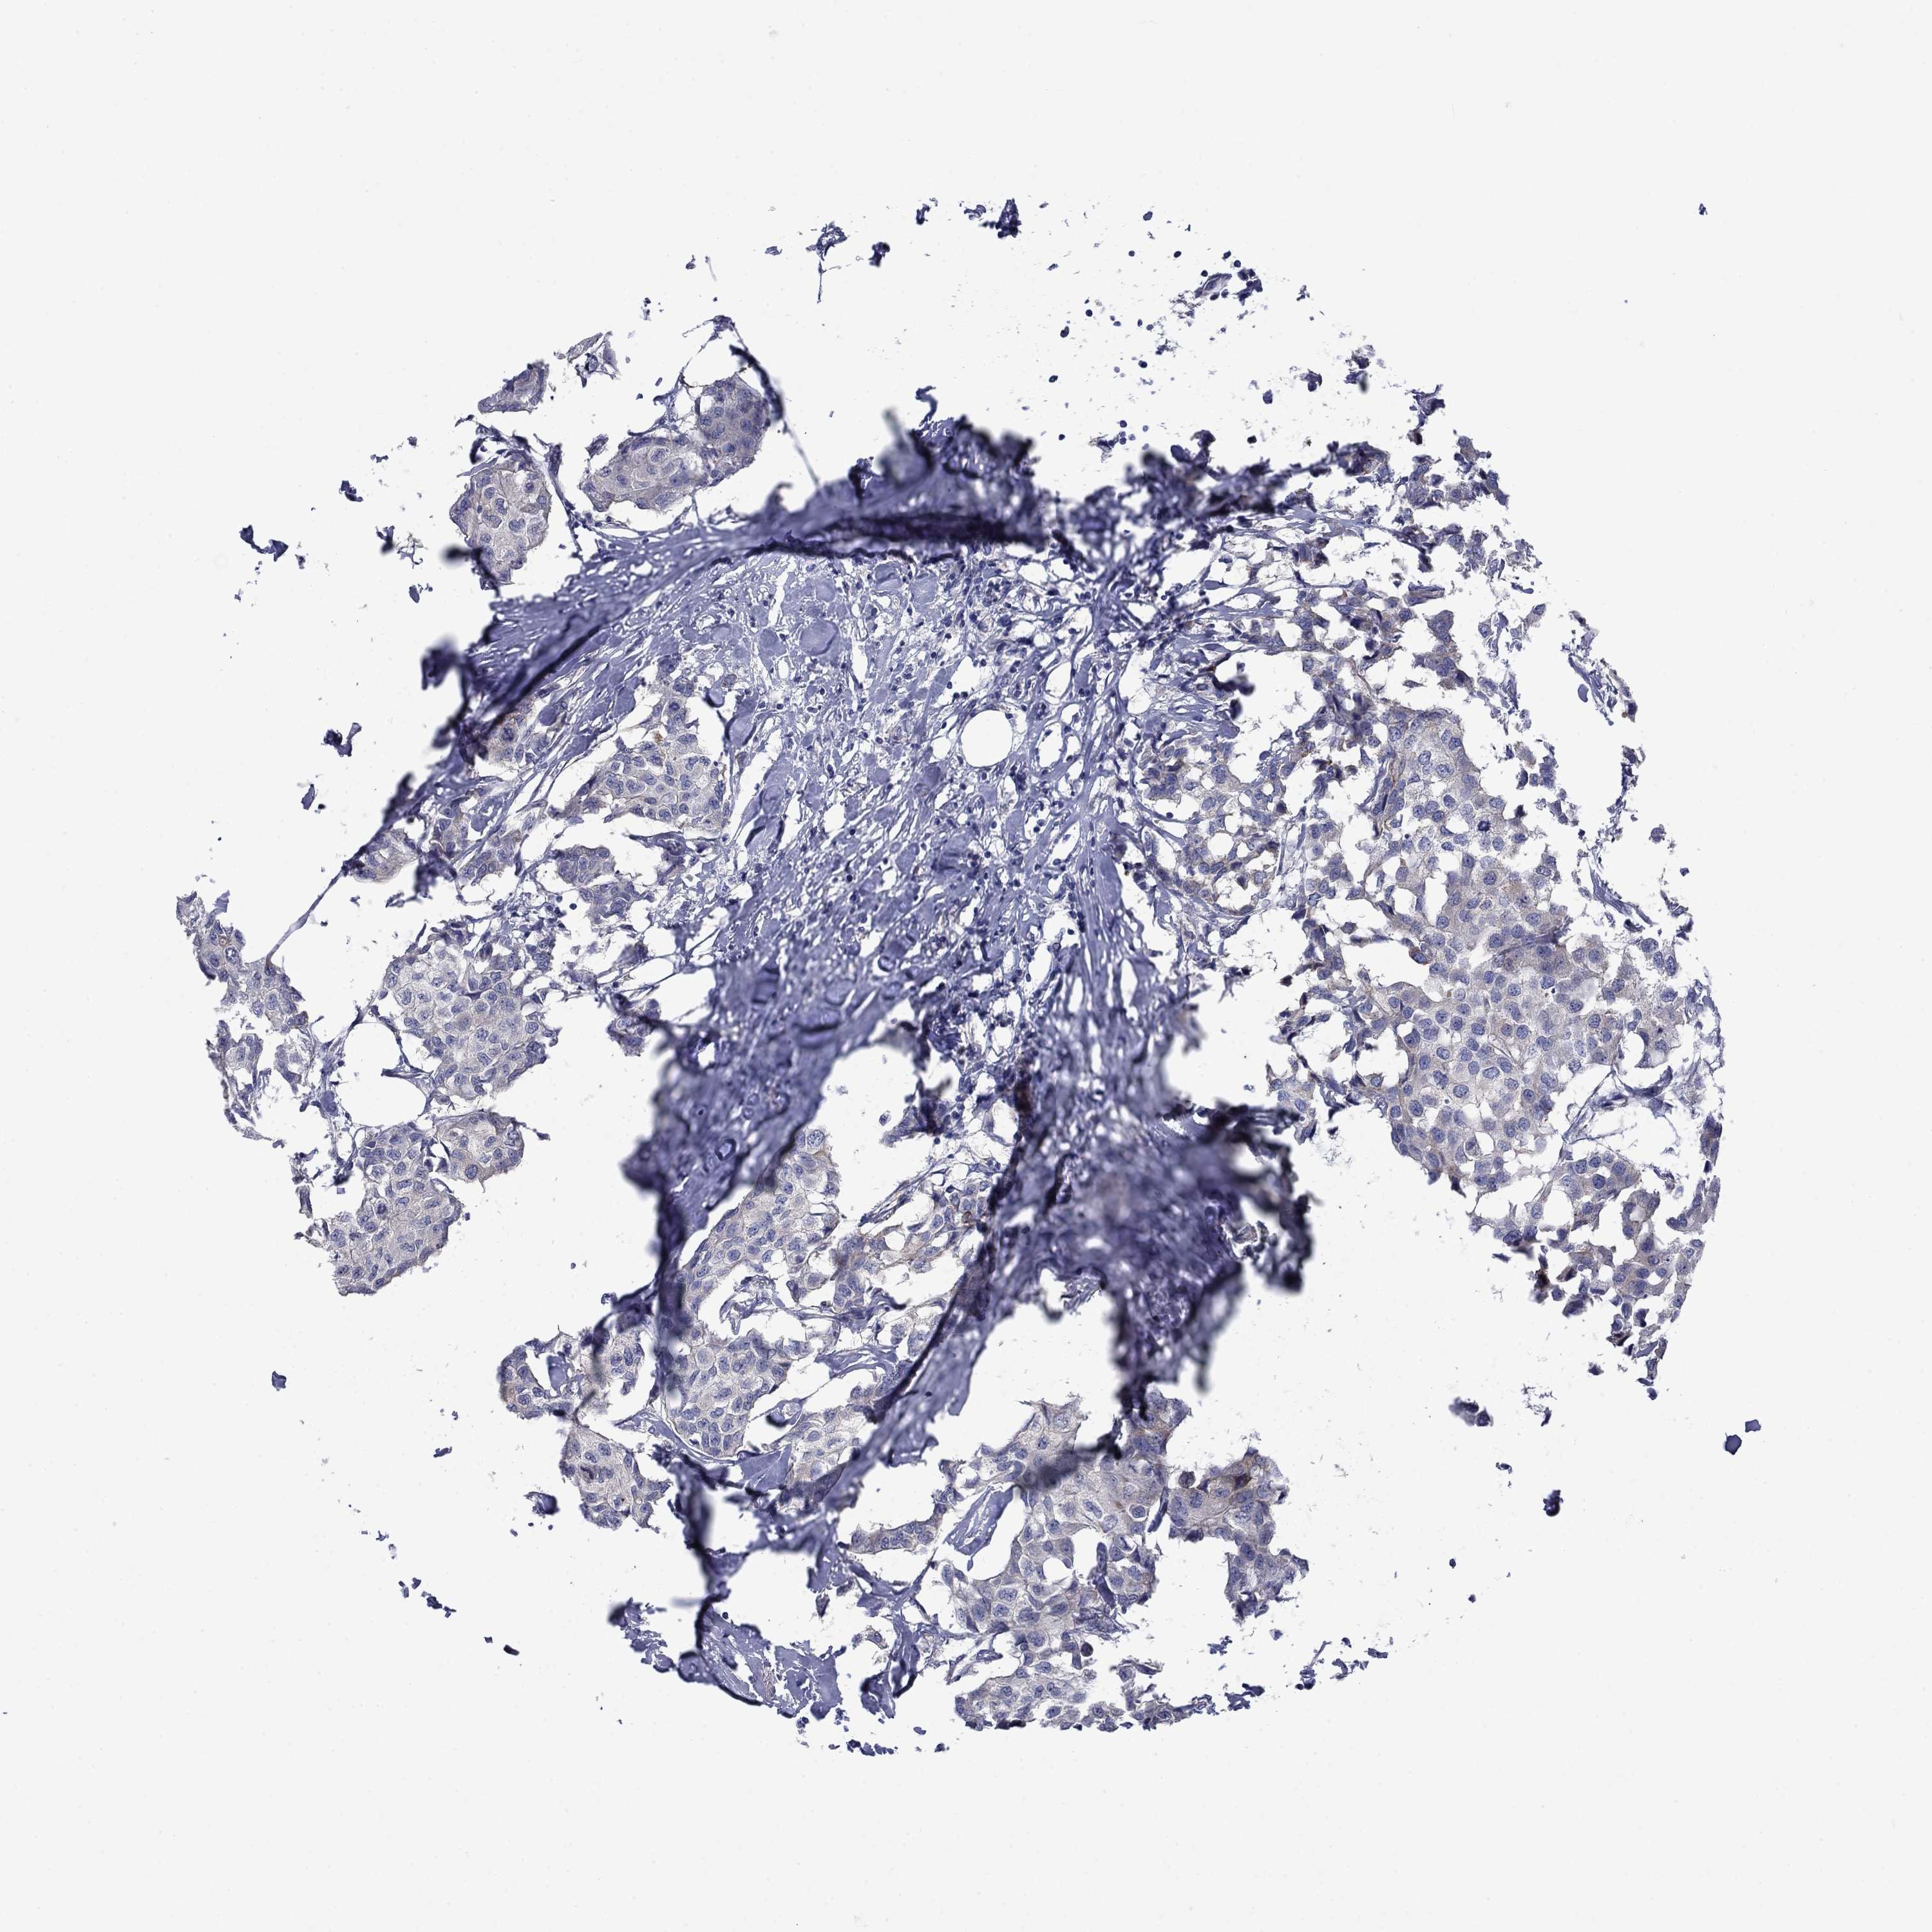

BRCA TCGA BRCA VALIDATION PROTEIN EXPRESSION

ANTIBODIES

AND

VALIDATION